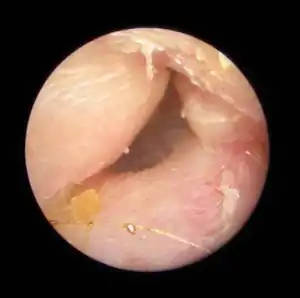

| Exostoses in the ear canal, as seen through otoscopy | |

Irritation from cold wind and water exposure causes the bone surrounding the ear canal to develop lumps of new bony growth which constrict the ear canal. Where the ear canal is actually blocked by this condition, water and wax can become trapped and give rise to infection. The condition is so named due to its prevalence among cold water surfers. Warm water surfers are also at risk for exostosis due to the evaporative cooling caused by wind and the presence of water in the ear canal.

- Decreased hearing or hearing loss, temporary or ongoing

- Increased prevalence of ear infections, causing ear pain

- Difficulty evacuating debris or water from the ear causing a plugging sensation